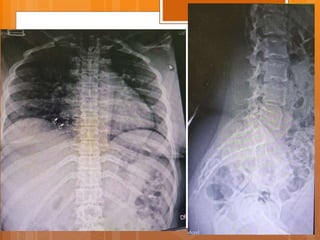

Case presentation  Female 21 y/o  Back pain from 1.5 years ago  Exacerbated after child delivery (9m ago)  Pain radiated to right leg from 7m ago

P/E  ↓L3 ,L4 force  right clonus  ↓ achilles DTR  QC DTR normal  Babinski sign normal  Intermittent Bladder dysfunction  Sensory normal